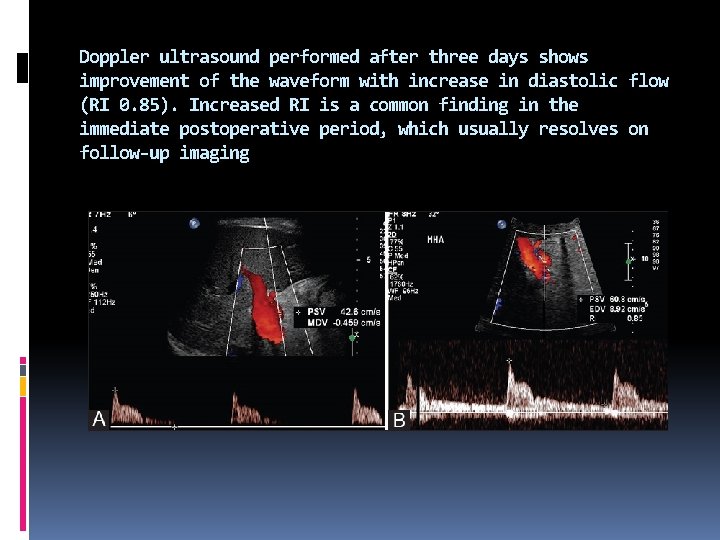

The most common transient hepatic arterial waveform abnormality seen in the immediate postoperative period is increased hepatic arterial RI, due to decreased diastolic flow. Increased RI (RI > 0. 8, absent or even reversed diastolic flow) is seen in almost half the patients immediately after liver transplantation. This can involve the main hepatic artery as well as its intrahepatic branches. The RI usually normalizes within 7 -15 days and is not associated with poor graft function. This transient elevation of RI is likely secondary to allograft edema, increased cold ischemia time, increased portal flow or vessel spasm

Figure 2 (A and B): (A) Transient increased hepatic arterial RI. Doppler ultrasound performed on the first postoperative day after liver transplantation shows absent diastolic flow (RI = 1) in the main hepatic artery (B) Transient increased hepatic arterial RI. Follow-up

Doppler ultrasound performed after three days shows improvement of the waveform with increase in diastolic flow (RI 0. 85). Increased RI is a common finding in the immediate postoperative period, which usually resolves on follow-up imaging